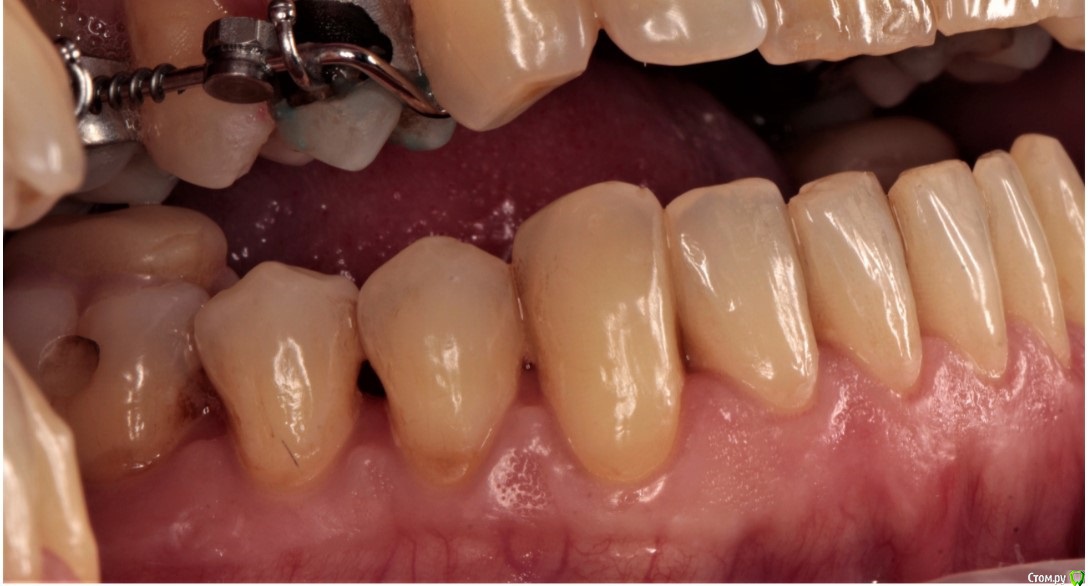

1. рецессии, клиновидный дефект, ВНЧС в результате неправильного прикуса (макрогнатия нижней и микрогнатия верхней челюсти)

2. год назад у меня был гингивит, переросший в некроз, приведший к полной потере сосочков нижней челюсти

так же мы понимаем, что сосочки это не только эстетика, но и важный функционал всей системы. И без них жить нельзя. При этом, технологии их восстановления, после некроза, не существует.

Я вижу вариант, полного протезирования всех зубов нижней челюсти, максимально закрыв отсутствующие сосочки. Если я понимаю правильно, то зачем тогда нам выпрямлять зубы нижней челюсти, травмируя кость и провоцируя дальнейшие рецессии? Не правильнее ли с помощью протезирования сразу придать им нужную форму и положение? Тем более раскрыв скученный перед у нас там дыры такие же как в боковых отделах будут...

сосочки утеряны вследствие пародонтита. Восстановить их почти нереально. Только ортопедически, изменив форму зубов.